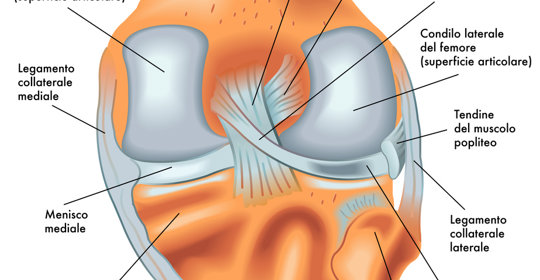

動脈炎:兒童血管炎、幹燥症血管炎